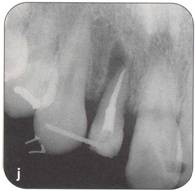

Fi 545e45f g 5-8i Radiographic evaluation of the donor tooth. Several angulations should be used to determine the likely fit of the donor tooth into the recipient site. If the first premolar is double-rooted, consider using the second premolar as a donor tooth. |

|